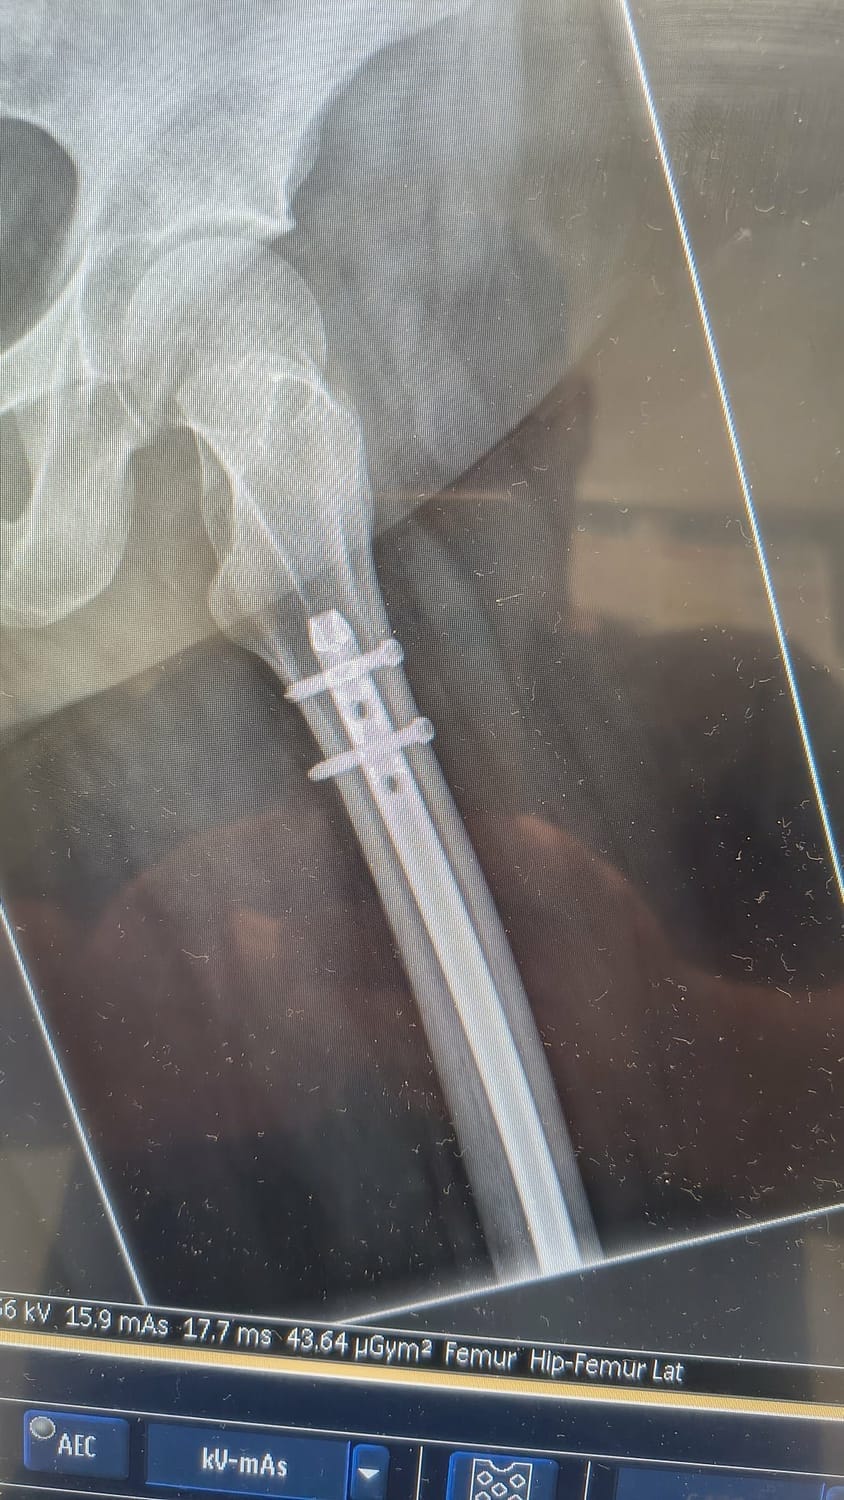

The skilled surgical team had to insert a 12-inch rod through my femur, stretching from near my hip right down to my knee, which was then secured firmly with bolts at each end to stabilize the fracture. Additionally, they had to thoroughly clean and enlarge the wound area where the bone broke through my skin, which left me with a substantial 21 staples in total.